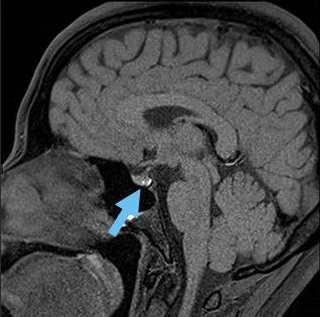

MRI検査では

- T1強調;50% 高信号(蛋白成分が多い)、50% 低信号

- T2強調;70% 高信号、30% 等-低信号

- T1+ Gd造影剤;造影効果なし、周囲辺縁のみ造影される